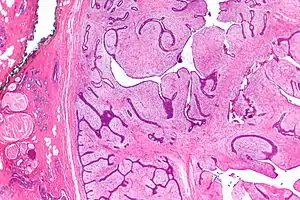

| Micrograph of a phyllodes tumor (right of image) with the characteristic long clefts and myxoid cellular stroma. Normal breast and fibrocystic change are also seen (left of image). H&E stain. |

Phyllodes tumors are a fibroepithelial tumor composed of an epithelial and a cellular stromal component. They may be considered benign, borderline, or malignant depending on histologic features including stromal cellularity, infiltration at the tumor's edge, and mitotic activity.[1] All forms of phyllodes tumors are regarded as having malignant potential. A large series from the M.D. Anderson Cancer Centre reported the incidence of each as benign (58%), borderline (12%), and malignant (30%). Malignant phyllodes tumours behave like sarcomas and can develop blood-borne metastases. Approximately 10% of patients with phyllodes tumours develop distant metastases and this can go up to 20% in patients with histologically malignant tumours.[2] The commonest sites for distant metastases are the lung, bone, and abdominal viscera. Rare sites of metastasis, such as to the parotid region, have also been described.[3]